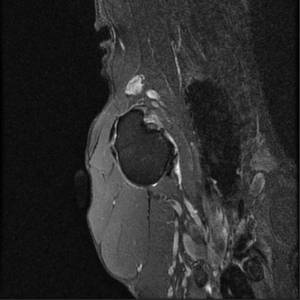

Main Gallery

Playing with a photo gallery function. It is possible to have multiple galleries, each within a namespace.